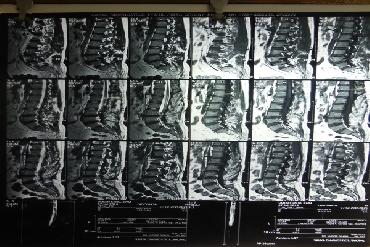

A herniated lumbar disc can push on spinal nerves and cause severe, shooting leg pain, numbness and/or weakness. A percutaneous disc removal (PDR) can remove a portion of the herniated disc that is compressing spinal nerves through a small incision in the skin. This minimally invasive approach uses a much smaller incision than traditional open spinal surgeries and avoids damage to the low back muscles.

In some cases, removing part of the herniated disc in a partial discectomy procedure can also prevent the disc from irritating the nerve.